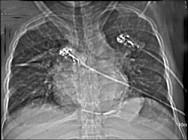

男性45岁,心悸气促乏力,下肢肿胀半年余,曾患肺结核,胸部CT扫描如图所示,请选择正确的选项为 ( )A、X线、CT为常用检查方法B、...

相关内容:男性,气促,下肢,半年,曾患,肺结核,胸部,扫描,如图,选项,常用,检查,方法